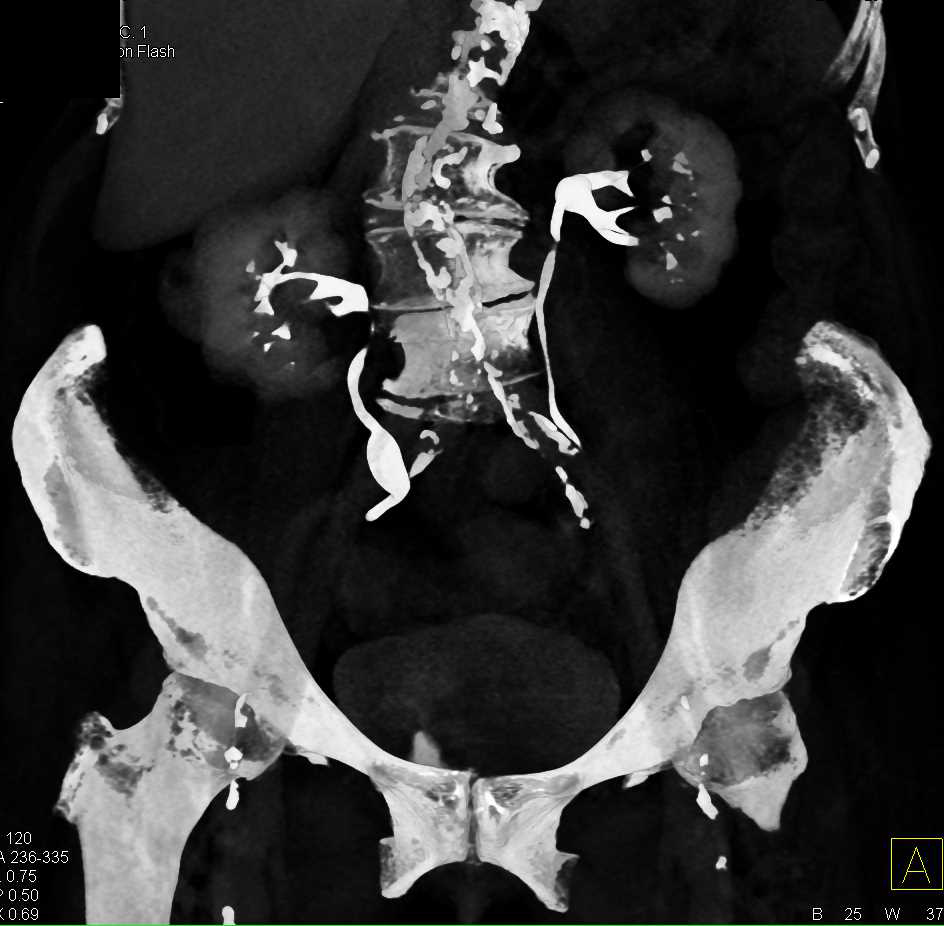

Multiple Bilateral Renal Angiomyolipomas in a Patient with Von Hippel-Lindau syndrome (VHL)